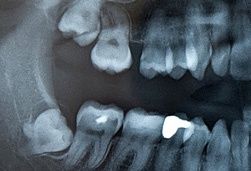

Diese Backenzähne kommen erst spät zur Entwicklung (15. - 21. Lebensjahr) und sind von der Natur wahrscheinlich als so eine Art Reserve gedacht. Bei den meisten Menschen (ca. 90%) reicht der Platz im Kiefer allerdings nicht aus, so dass die Weisheitszähne ganz oder teilweise im Kiefer eingeschlossen bleiben.

• Lehnt sich ein Weisheitszahn an seinen Nachbarn in der Tiefe an, so kann dieser Zahn beschädigt werden – die Wurzel des Nachbarn löst sich auf – der Zahn kann dann meist nicht mehr gerettet werden.

• Sind Weisheitszähne durchgebrochen, also sichtbar und stehen sehr eng am Nachbarzahn, so ergibt sich häufig ein Zwischenraum, der nicht gut zu reinigen ist – Karies droht.